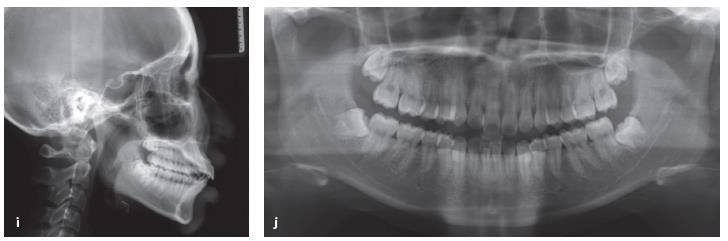

Một bệnh nhân nữ 17 tuổi có sai khớp cắn loại II với sự nhô ra của hàm trên và hàm dưới và chen chúc nhẹ (Hình 13-16a đến 13-16j).

Hồ sơ trước xử lý. Bệnh nhân có một sai khớp cắn loại II với hàm trên và hàm dưới nhô trước và chen chúc ít

Hồ sơ tiến độ tại tháng 14 với khoảng nhổ răng được đóng lại. Một số tipping phía gần của răng hàm lớn thứ nhất được thấy. (p) Tiến hành chụp phim toàn cảnh panorama cho thấy các răng hàm lớn thứ nhất đã tipping về phía gần vào vị trí nhổ răng.

Tuy nhiên, chụp ảnh toàn cảnh panorama tại thời điểm đó cho thấy tất cả các răng hàm lớn thứ nhất đã tipping về phía gần vào khoảng nhổ răng .